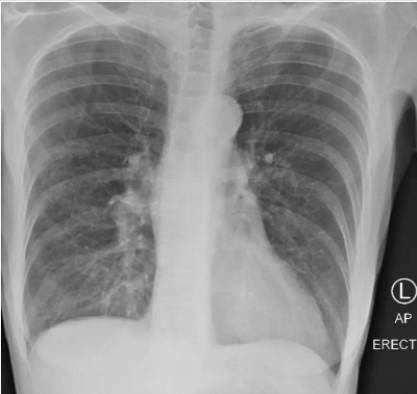

Рентгенівський знімок курця був нечітким, в той час, як рентгенівський знімок пацієнта з COVID виглядав майже повністю білим. Помутніння легенів зазвичай вказує на те, що вони наповнені такими речовинами, як рідина або бактерії, а також щільними рубцями і ушкодженнями, пояснила лікар.

«Легені після коронавірусу виглядають гірше, ніж легені найжахливішого курця, які ми коли-небудь бачили», – підкреслила вона.Легені курця